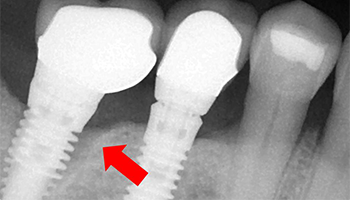

How to identify dental implants by x ray

There are three common types of dental implants you can choose from: endosteal, subperiosteal, and zygomatic. The endosteal is the safest and most common, followed by the subperiosteal, and the zygomatic is the last and most complex.

Dental Implant System is a set of certified medical devices that professional dentists use to anchor dentures or replace missing teeth. An implant system consists of different types of dental implants, different dental superstructures, and implant instruments.